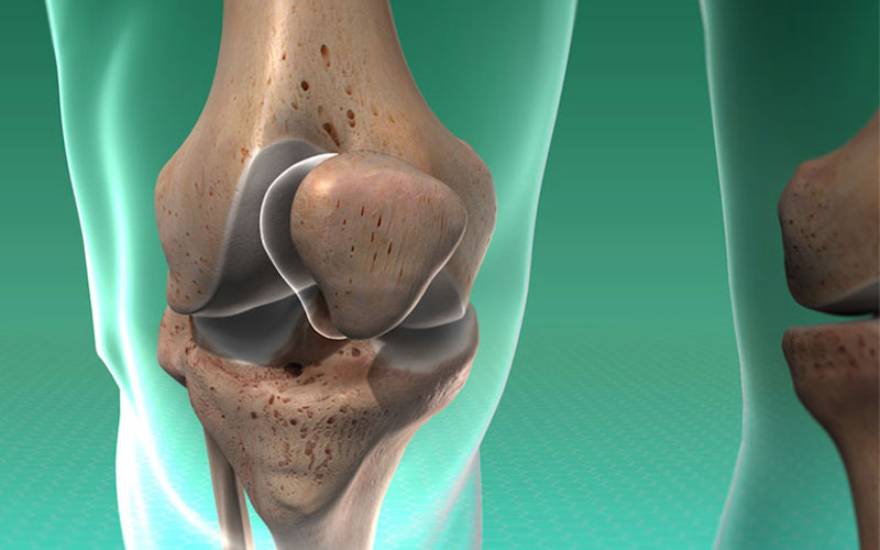

슬개골(Patella)은 무릎 관절 앞부분을 보호하는 뼈로, 무릎을 펴거나 굽힐 때 지렛대 역할을 하여 다리의 움직임과 균형 유지를 돕는 핵심적인 부위입니다. 슬개골 골절은 이 뼈에 금이 가거나 여러 조각으로 부서지는 심각한 상태를 의미합니다. 골절이 발생하면 무릎 관절의 가동 범위가 급격히 줄어들며, 일상적인 활동에 큰 통증과 제약을 유발합니다.

무릎 관절의 슬개골 구조 이미지